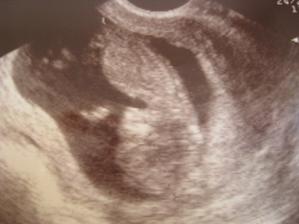

27.6.2008 - dovolená byla žůžo! Mamka mě vozila na tom... nóó.. na kole. To se mi moc líbilo, jenom nevím, jestli mamce taky, protože pořád nadávala, že jí to netáhne do kopce. Taky aby jo, vždyť já už jsem pořádnej kus Píďalky. O dovolené jsem se činila co to jenom šlo a tak když jsme šli na další focení (aby byl nějakej materiál, až zase budou vyhlašovat ty osobnosti století nebo tak něco) k tomu pánovi v bílém, měřila jsem už celých 6 cenťáků a srdíčko mi tlouklo 158x za minutu. Nevím, jestli se mamka těšila na nějaký vzrůšo, ale ten - jo, "pandoktor" mu říkaj - jí oznámil, že všechny krevní testy má v nudném průměru